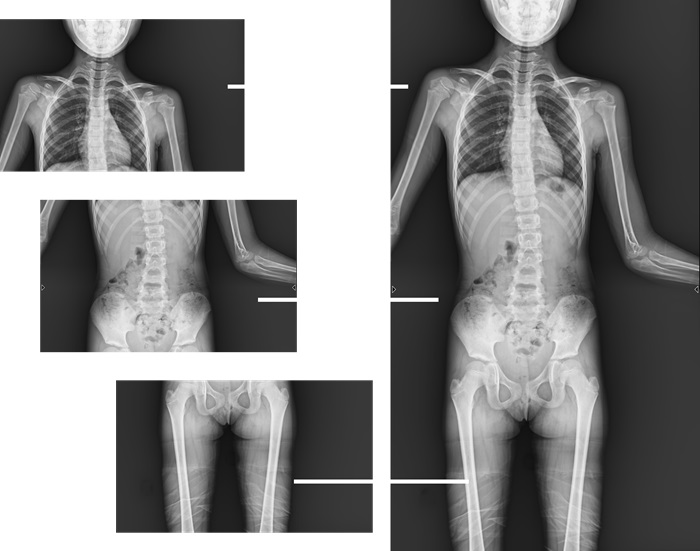

而且,影像采集幅面大,17×17英寸超大視野可覆蓋成年人的全胸全腹,并且能在連續(xù)動態(tài)中實(shí)時高清點(diǎn)片,從而達(dá)到精準(zhǔn)診斷的目的。設(shè)備靈活高效的多維度運(yùn)動設(shè)計(jì),也帶來了更加智能化、人性化操作體驗(yàn),可大幅提升檢查效率。

與此同時,普利德動態(tài)平板DRF還具有全身拼接功能,尤其適用于全脊柱和全下肢攝影,為臨床提供高精度圖像,輔助脊柱畸形矯形治療、康復(fù)檢查。